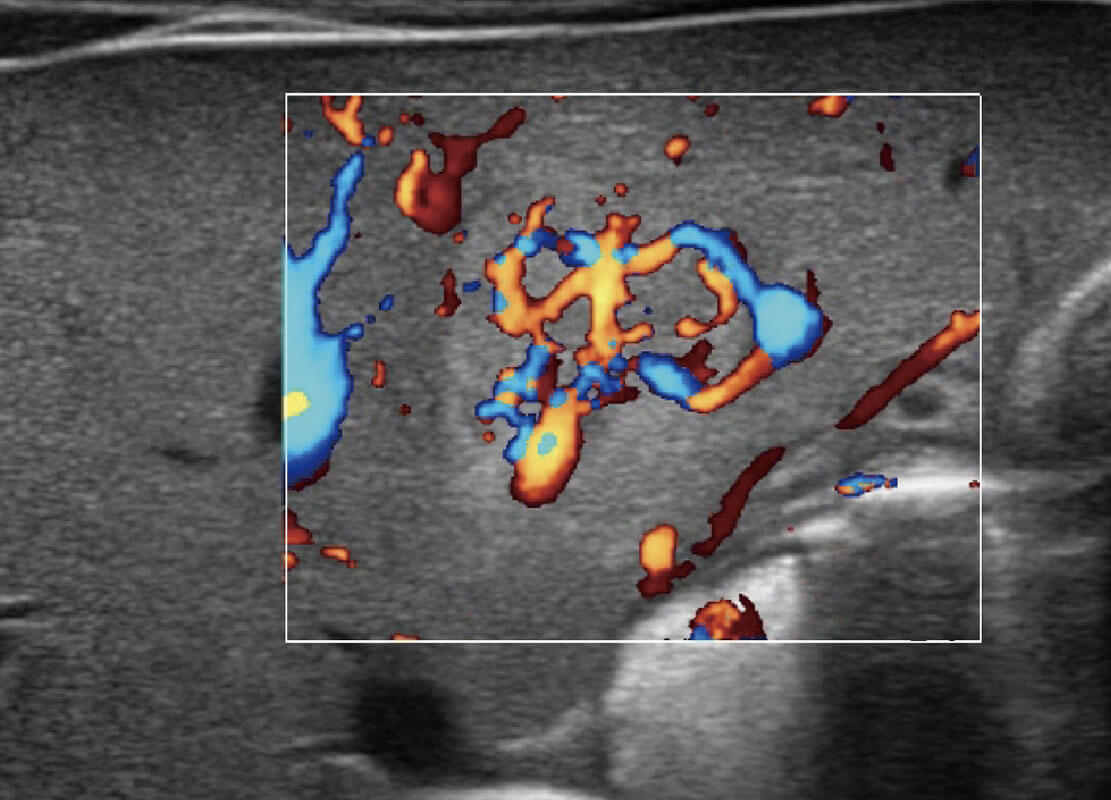

P60搭载一系列胎儿心脏成像技术,实现精细的胎儿心脏评估。

四腔心血流